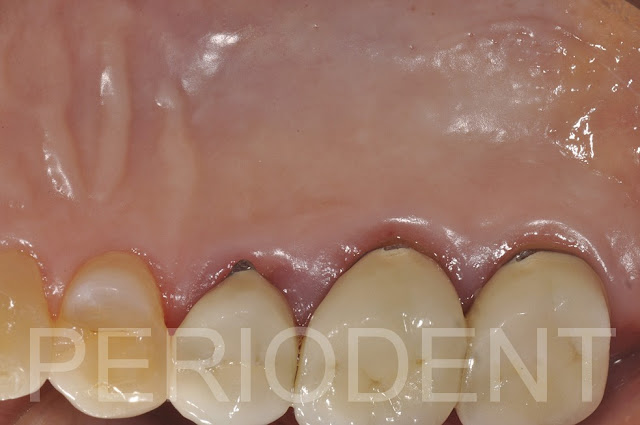

10天拆線時